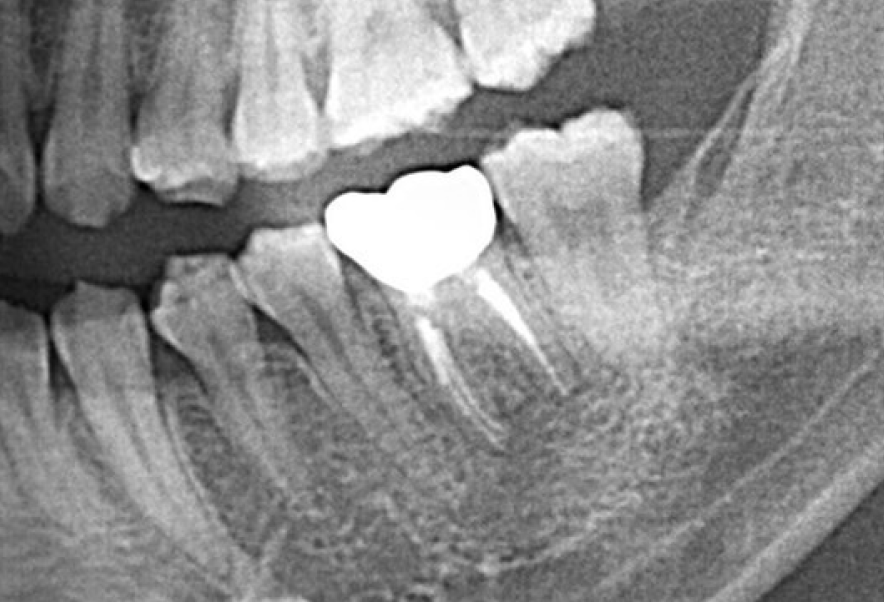

Before

After

他院で抜歯と診断された歯の精密根管治療